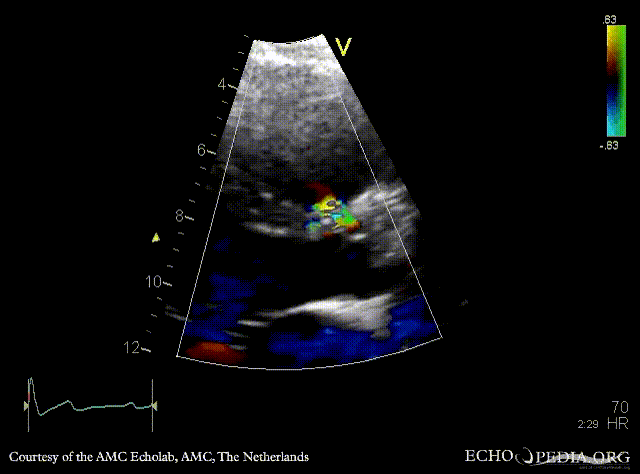

Perimembraneous VSD

E00683.gif

PLAX with Color Doppler Continuous-wave Doppler signal of flow through ventricular septum defect